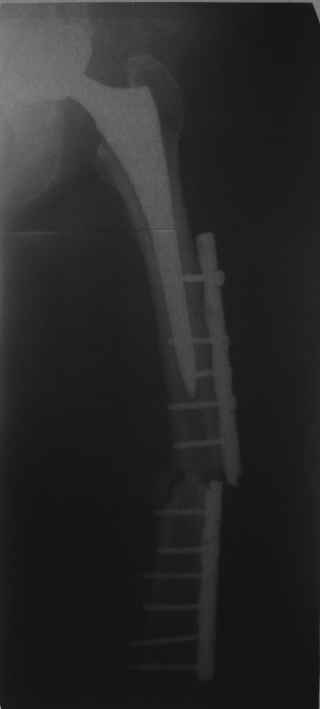

[Ortho] Перипротезный перелом

Обещанные ранее снимки Заранее спасибо.